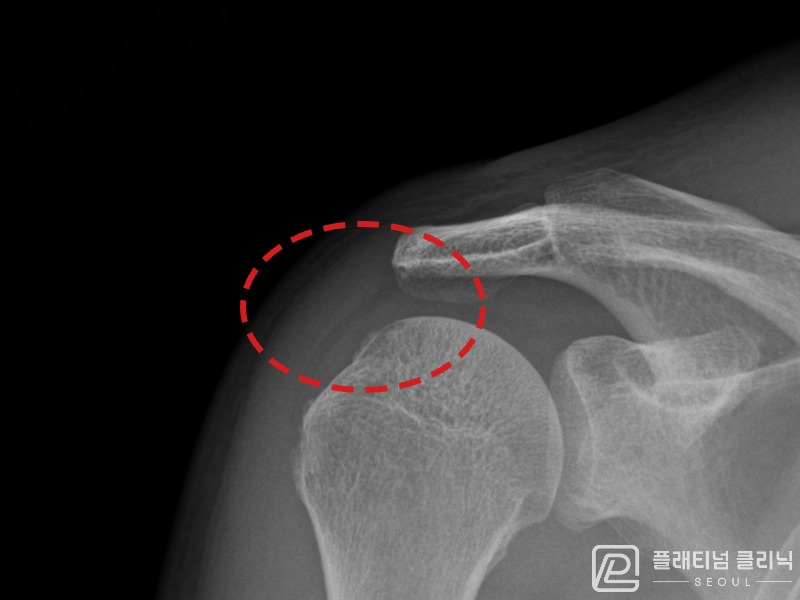

[촬영시기:21.08.30~21.09.09]

[석회분쇄흡입술] 우측 어깨 통증으로 밤잠을 못 이루고 팔을 올리기 어려워진 30대 여성 환자로, X-ray에서 우측 극상근건 내 석회 침착이 확인되어 석회분쇄흡입술을 시행하였습니다.